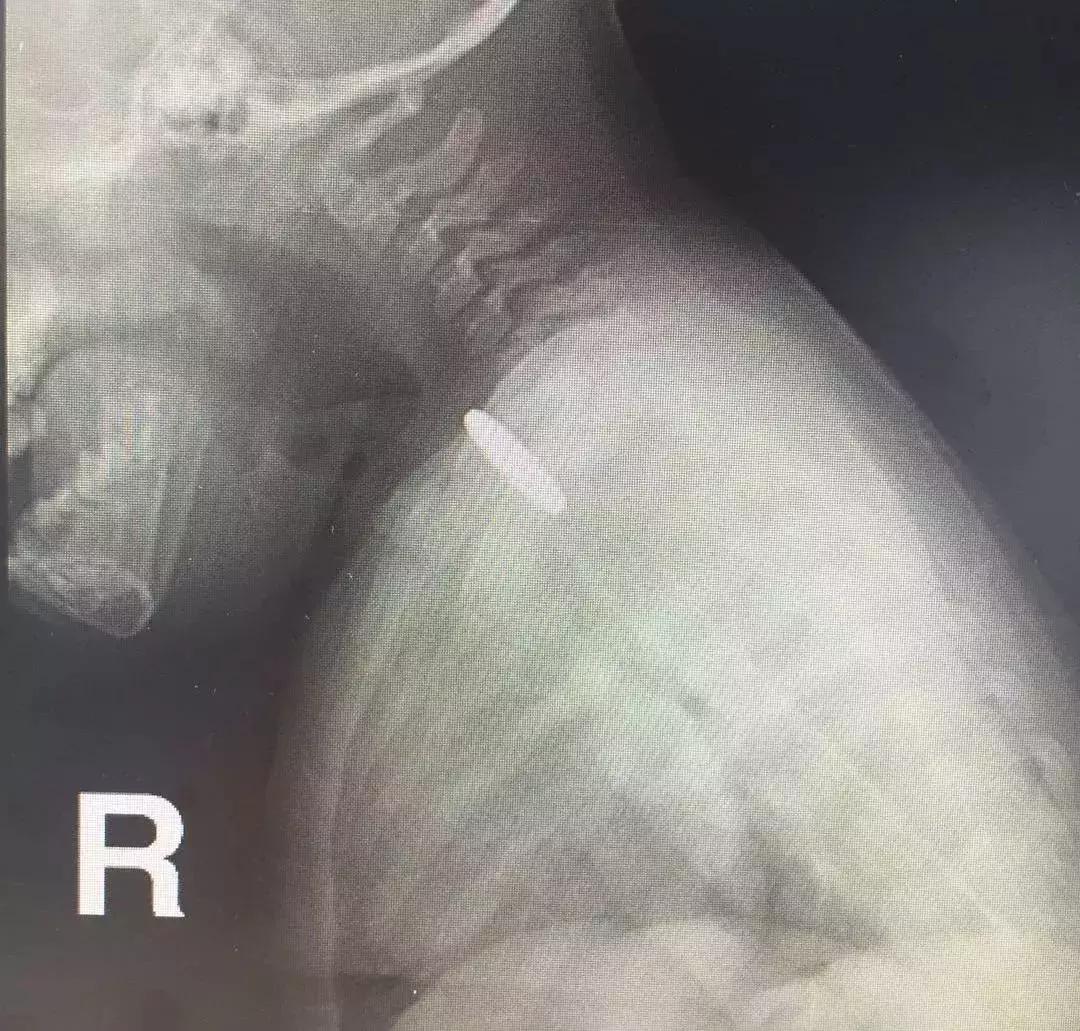

麻醉科文先杰博士决定为心心做气管插管麻醉,堵住可能存在的风险点。气管插管是指将一特制的气管内导管经口腔或者鼻子置入气管,以保证气道通畅。

由于孩子的气道很很窄,小儿气管插管并非一件易事。但是,文先杰博士凭借过硬的技术顺利完成。

孩子的食管很窄,尤其是食道入口位置不够1厘米,消化内科副主任医师陈渭选用了最小的8毫米直径的内镜。

慢慢进入,在食道入口处见到了那枚堵住食管的硬币,视察到心心的食道没有损伤之后,用专用的异物钳小心翼翼取出硬币,一气呵成,全程不到2分钟,整个过程患儿并没有痛苦。